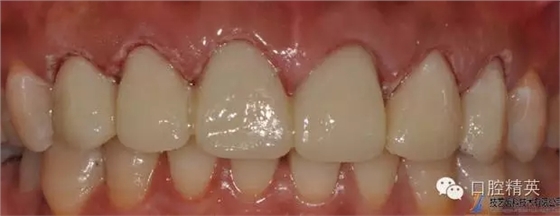

原金屬烤瓷冠